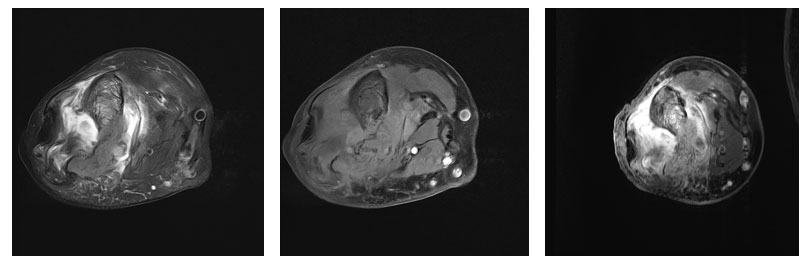

Ameliyat Öncesi: MR görüntülerinde ciddi kemik harabiyeti ve çevresinde yaygın ödem izlenmekte.

Akciğer Kanseri Kol Kemiği Metastazı | Distal Humerus Protez Uygulaması